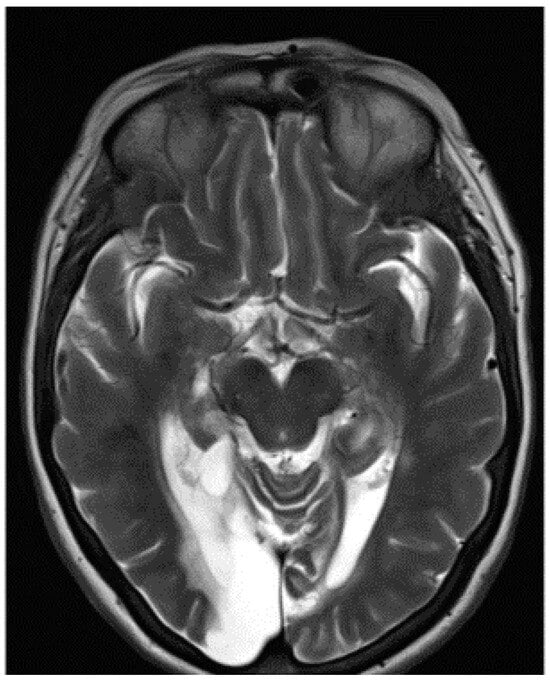

The visual acuity of each eye for distance was 6/12. Colour vision was intact when tested with the Farnsworth–Munsell 15D test, but MH could not read the Ishihara colour chart. This suggested a diagnosis of simultanagnosia. The optic discs were slightly pale. No further abnormal signs were found in the examination of the nervous system. The cerebral angiogram was normal. The management comprised antiplatelet therapy, antihypertensive medication and, in recent years, treatment of diabetes mellitus. An MRI scan confirmed bilateral occipital lobe infarction when it became available eleven years after the onset of her symptoms (Figure 3).

Figure 3.

MRI scan of the brain showing encephalomalacia in the occipital and posterior temporal lobes bilaterally and the left superior cerebellum with bilateral thalamic infarcts.

3.3. Structural MRI Report

An MRI scan of the brain revealed multiple areas of encephalomalacia involving both the occipital and posterior medial temporal lobes, which were larger on the right, including the fusiform and lingual gyri bilaterally, the left superior cerebellum, and small lacunar infarcts within the thalami bilaterally. Within the temporal lobe, the damage involved the right lateral and medial occipito-temporal gyrus, the posterior body of the right hippocampus, and both parahippocampal gyri posteriorly (Figure 3). The appearance was consistent with chronic infarcts within the posterior circulation. Given the patient’s history of trauma and headache and the young age of onset, this was most likely secondary to vertebral artery dissection.